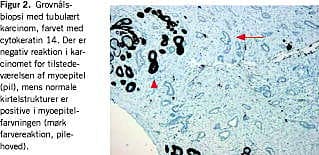

En meget anvendelig gruppe af antistoffer er rettet mod de myoepiteliale celler, som ligger yderst mod basalmembranen i normale gangstrukturer. Påvisning af myoepiteliale celler udelukker invasiv cancer. Antistofferne kan derfor anvendes til at skelne mellem karcinom in situ og invasivt karcinom eller mellem et radialt ar og en tubulær cancer (Figur 2 ). Det er dog vigtigt at erindre, at manglende påvisning af myoepiteliale celler skal fortolkes med stor varsomhed og under hensyntagen til morfologien. Det er derfor også en god ide at anvende to eller flere antistoffer i hvert tilfælde. De mest anvendte antistoffer er rettet mod cytokeratin 14 eller smooth muscle myosin heavy chain (SM-MHC), men også p63- og smooth muscle actin -antistoffer anvendes.